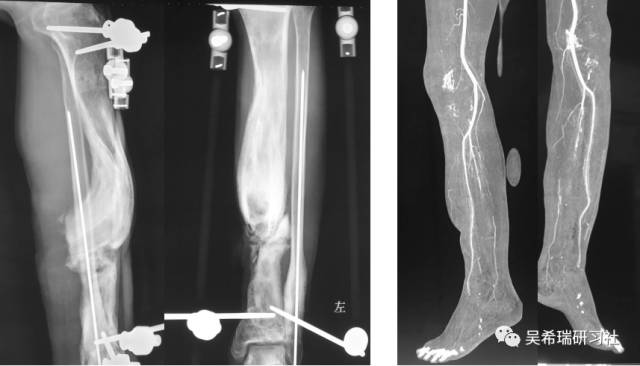

双下肢车祸外伤保肢的理由是足底皮肤好

TIPS:清创&盐水冲洗(不用双氧水)VSD骨水泥技术&开放植骨单边外固定架(下胫腓联合固定)早期下地 生理应力 + 机械应力游离植皮 / 不用皮瓣清创时游离皮质骨去除胫跖骨牵引技术防治&纠正足下垂